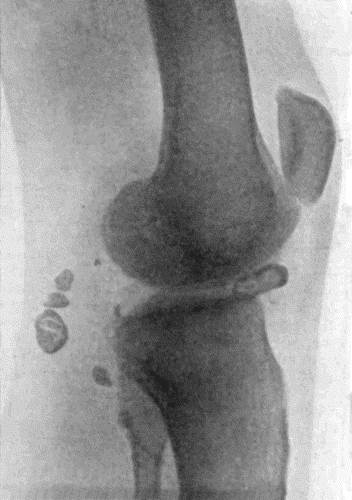

166.Radiogram of Multiple Loose Bodies in Knee-joint 540

167.Loose Body from Knee-joint 541